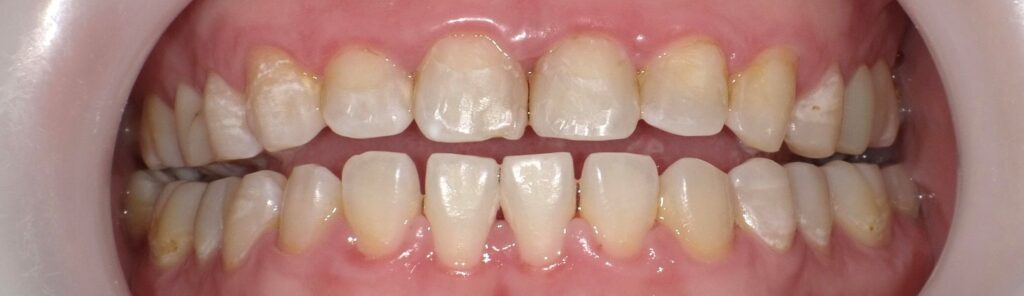

ホームホワイトニング後の口腔内写真です。

ご自宅でのケアを継続して行うことで、さらに透明感がアップしました。

初回実施から24日後に2回目のホワイトニングを実施しました。

2回目施術後の口腔内です。

(少し写真の角度が違って比較しにくくてすみません)

さらに透明感が出て、白さがしっかり維持されています。

初回実施前の写真と比較すると、より変化が分かりやすいと思います。